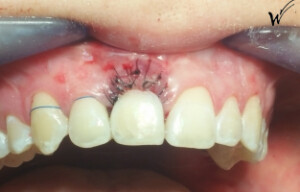

Cas clinique « SMILE RED FLAG MEI » : Traitement de remplacement d’une dent du sourire par un implant en Mise en Esthétique Immédiate. Visualisation de la version définitve de la couronne sur implant avec un cosmétique en céramique.

Cicatrisation des tissus et résultat clinique à la pose de la couronne céramique